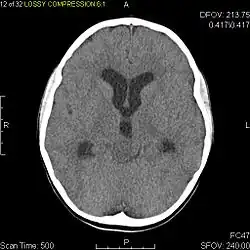

Usually – depending on the interview of the patient and after a clinical exam which includes a neurological exam and an ophthalmological exam – a CT scan and/or an MRI scan will be performed to confirm the presence of a tumor. They are usually easily distinguishable from normal brain structures using these imaging techniques. A special dye may be injected into a vein before these scans to provide contrast and make tumors easier to identify. Pilocytic astrocytomas are typically clearly visible on such scans, but it is often difficult to say based on imaging alone what type of tumor is present.

Pilocytic astrocytomas are often cystic tumors, and, if solid, tend to be well-circumscribed.

Under the microscope, the tumor is seen to be composed of bipolar cells with long "hair-like" GFAP-positive processes, giving the designation "pilocytic" (that is, made up of cells that look like fibers when viewed under a microscope[6]). Some pilocytic astrocytomas may be more fibrillary and dense in composition. The presence of Rosenthal fibers,[7] eosinophilic granular bodies, and microcysts can often be seen. Myxoid foci and oligodendroglioma-like cells may also be present, though these are not specific to pilocytic astrocytoma. Long-standing lesions may show hemosiderin-laden macrophages and calcifications.